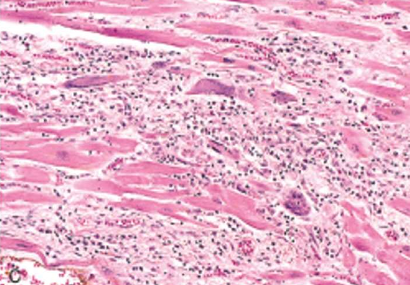

Rheumatic Myocarditis

Aschoff bodies are seen between myocardial bundles as paravascular fusiform collection of mononuclear cells around fibrinoid necrosis